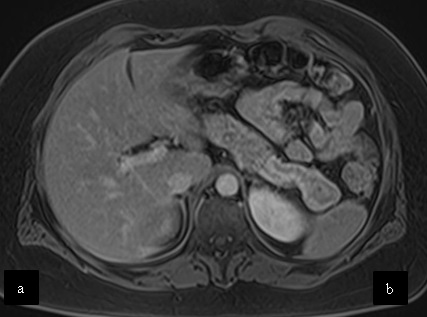

Caso 3

Mujer de 36 años que ingresa a Hospital Sanatorio Franchin el 11 de octubre de 2023 de forma programada para realización de duodeno pancreatectomía cefálica por tumor de cabeza de páncreas en estudio. Refiere hallazgo de lesión en forma incidental durante estudio de control hace dos meses por presentar antecedentes familiares (neoplasia endocrina múltiple). Se interna para manejo quirúrgico. Estudios de tomografía revelan formación nodular localizada en cabeza y cuerpo pancreático de paredes gruesas que mide 24 x 28 mm, que en resonancia se muestra hiperintensa en T2 y realce periférico luego de la administración de contraste endovenoso. Presenta restricción en la difusión con caída de la señal ADC, por lo que se vincula con una lesión de alta celularidad.

Estudio histopatológico reveló neoplásica de estirpe neuroendocrina bien delimitada.

La resonancia magnética es el otro estudio de imagen no invasivo que nos permite la detección de la lesión con una sensibilidad mayor que la de la tomografía, del 85% al 95%, donde los insulinomas presentan un realce tras la administración de contraste con gadolinio y secuencias T1 sin contraste son lesiones hipointensas y en secuencias T2 son hiperintensas.

La resonancia magnética confirmó aún más el diagnóstico de las lesiones ya previamente visualizadas en tomografía en esta revisión, con realce de las lesiones en secuencias T1 y contraste con gadolinio, y en las secuencias funcionales con restricción de la lesión y caída de la señal en el mapa de ADC.